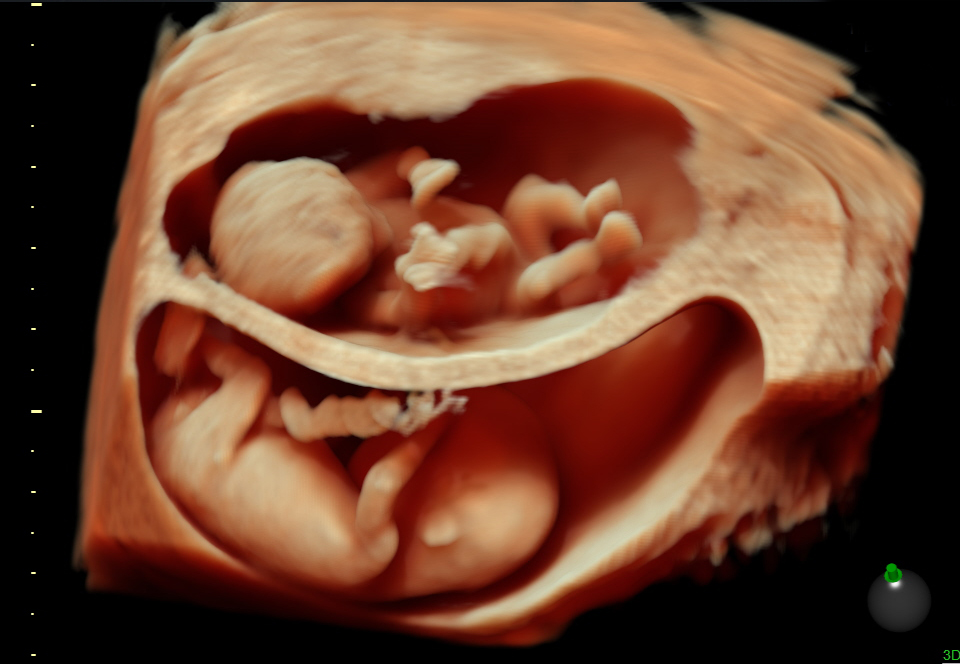

Un embarazo múltiple se confirma por medio de un ultrasonido. En ocasiones, la madre siente que puede estar esperando más de un bebé por el tamaño de su útero o la intensidad de sus síntomas. Un examen de sangre también puede determinar si hay más de un bebé en tu vientre.

Hace varias décadas, la mayoría de las mujeres que esperaban más de un niño no lo sabían hasta el momento del parto. Hoy día es raro que una mujer se entere de que espera más de un bebé al dar a luz. Las futuras mamás lo descubren al hacerse una ecografía o ultrasonido, normalmente durante el primer trimestre.

Tu médico probablemente te recomendará una ecografía durante ese primer trimestre si cree que estás más grande de lo común para esa etapa del embarazo. Las ecografías son útiles para determinar el tiempo que llevas realmente embarazada y si tu tamaño se debe a que esperas más de un bebé.

Si quedaste embarazada después de recibir un tratamiento de fertilidad como, por ejemplo, una fertilización in vitro, lo más probable es que te hagan una ecografía durante las primeras ocho semanas para contar el número de embriones. Las ecografías son casi infalibles cuando se trata de revelar embarazos múltiples, especialmente después de 6 a 8 semanas de embarazo. Sin embargo, cuantos más bebés lleves en el útero, más fácil es que alguno no se vea durante la ecografía.

Si no puedes o no quieres hacerte estas pruebas, un ultrasonido normalmente suele aclarar si los bebés que esperas son mellizos o gemelos al comprobar la existencia de una o dos placentas y verificar si los dos bebés son del mismo sexo. Un técnico experimentado que realice una ecografía transvaginal (con un aparato que se mete por la vagina) entre las semanas 9 y 14 puede determinar con casi el 100 por ciento de seguridad si los bebés comparten una sola placenta. (La tasa de acierto baja hasta el 90 por ciento en el segundo trimestre porque el útero está más lleno).